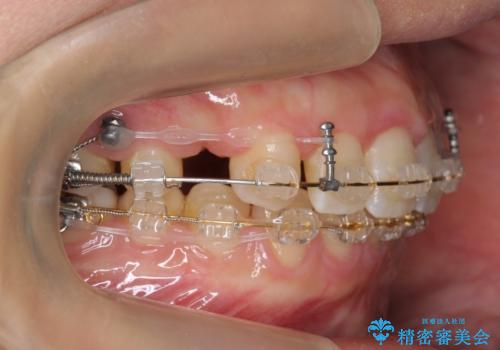

- 審美装置

レントゲンで、右上4番の近心の垂直的骨欠損があり、抜歯を行うこととしました。

short faceであり、結果上顎の臼歯を近心に大きくロスさせることになったたため、非常に長く治療期間はかかりました。

右上4の垂直性骨欠損については再生療法を行う選択肢もありました。

しかし、過蓋咬合であり、咬頭対咬頭の咬合では根本的な解決は見込めないことから、矯正治療を希望されていたこともあり、相談の上抜歯しました。